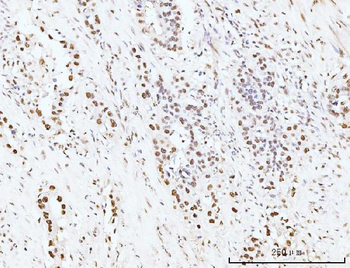

- PPM1D Rabbit Polyclonal Antibody [orb704535]Featured

IF, IHC-Fr, IHC-P

Human, Mouse, Rat

Mouse, Rat

Rabbit

Polyclonal

Unconjugated

100 μl, 50 μl, 200 μl - HSC70 Mouse Monoclonal Antibody [orb704174]Featured